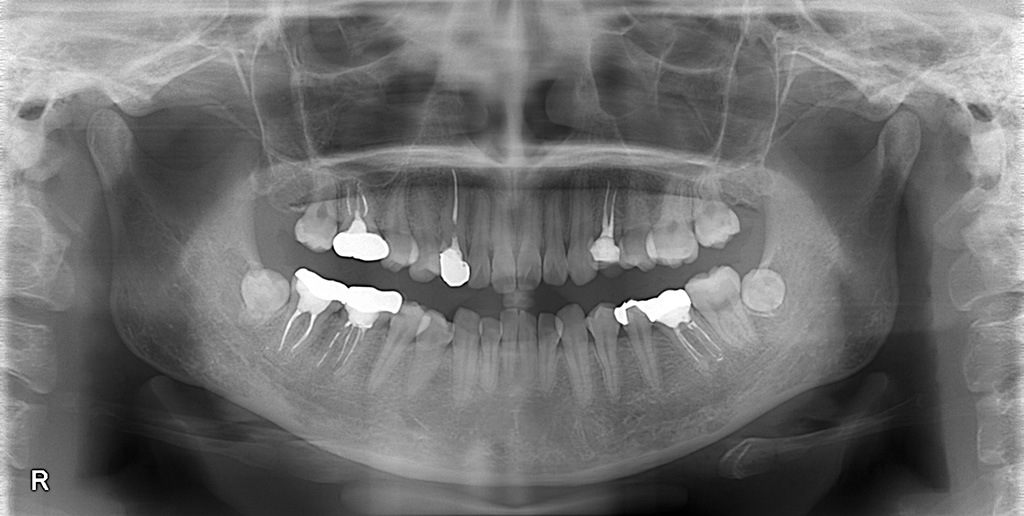

修復物が多いと、

どうしても フロスが引っかかりやすいポイント が増え、

患者さんの挫折につながりやすくなります。

そのため、まずは

「どこで引っかかりやすいか」を

一緒に確認・共有すること が大切。

ポイントを理解したうえで指導すると、

成功体験につながり、継続しやすくなります。

このタイプには後述の “輪っかフロス” をおすすめしています。